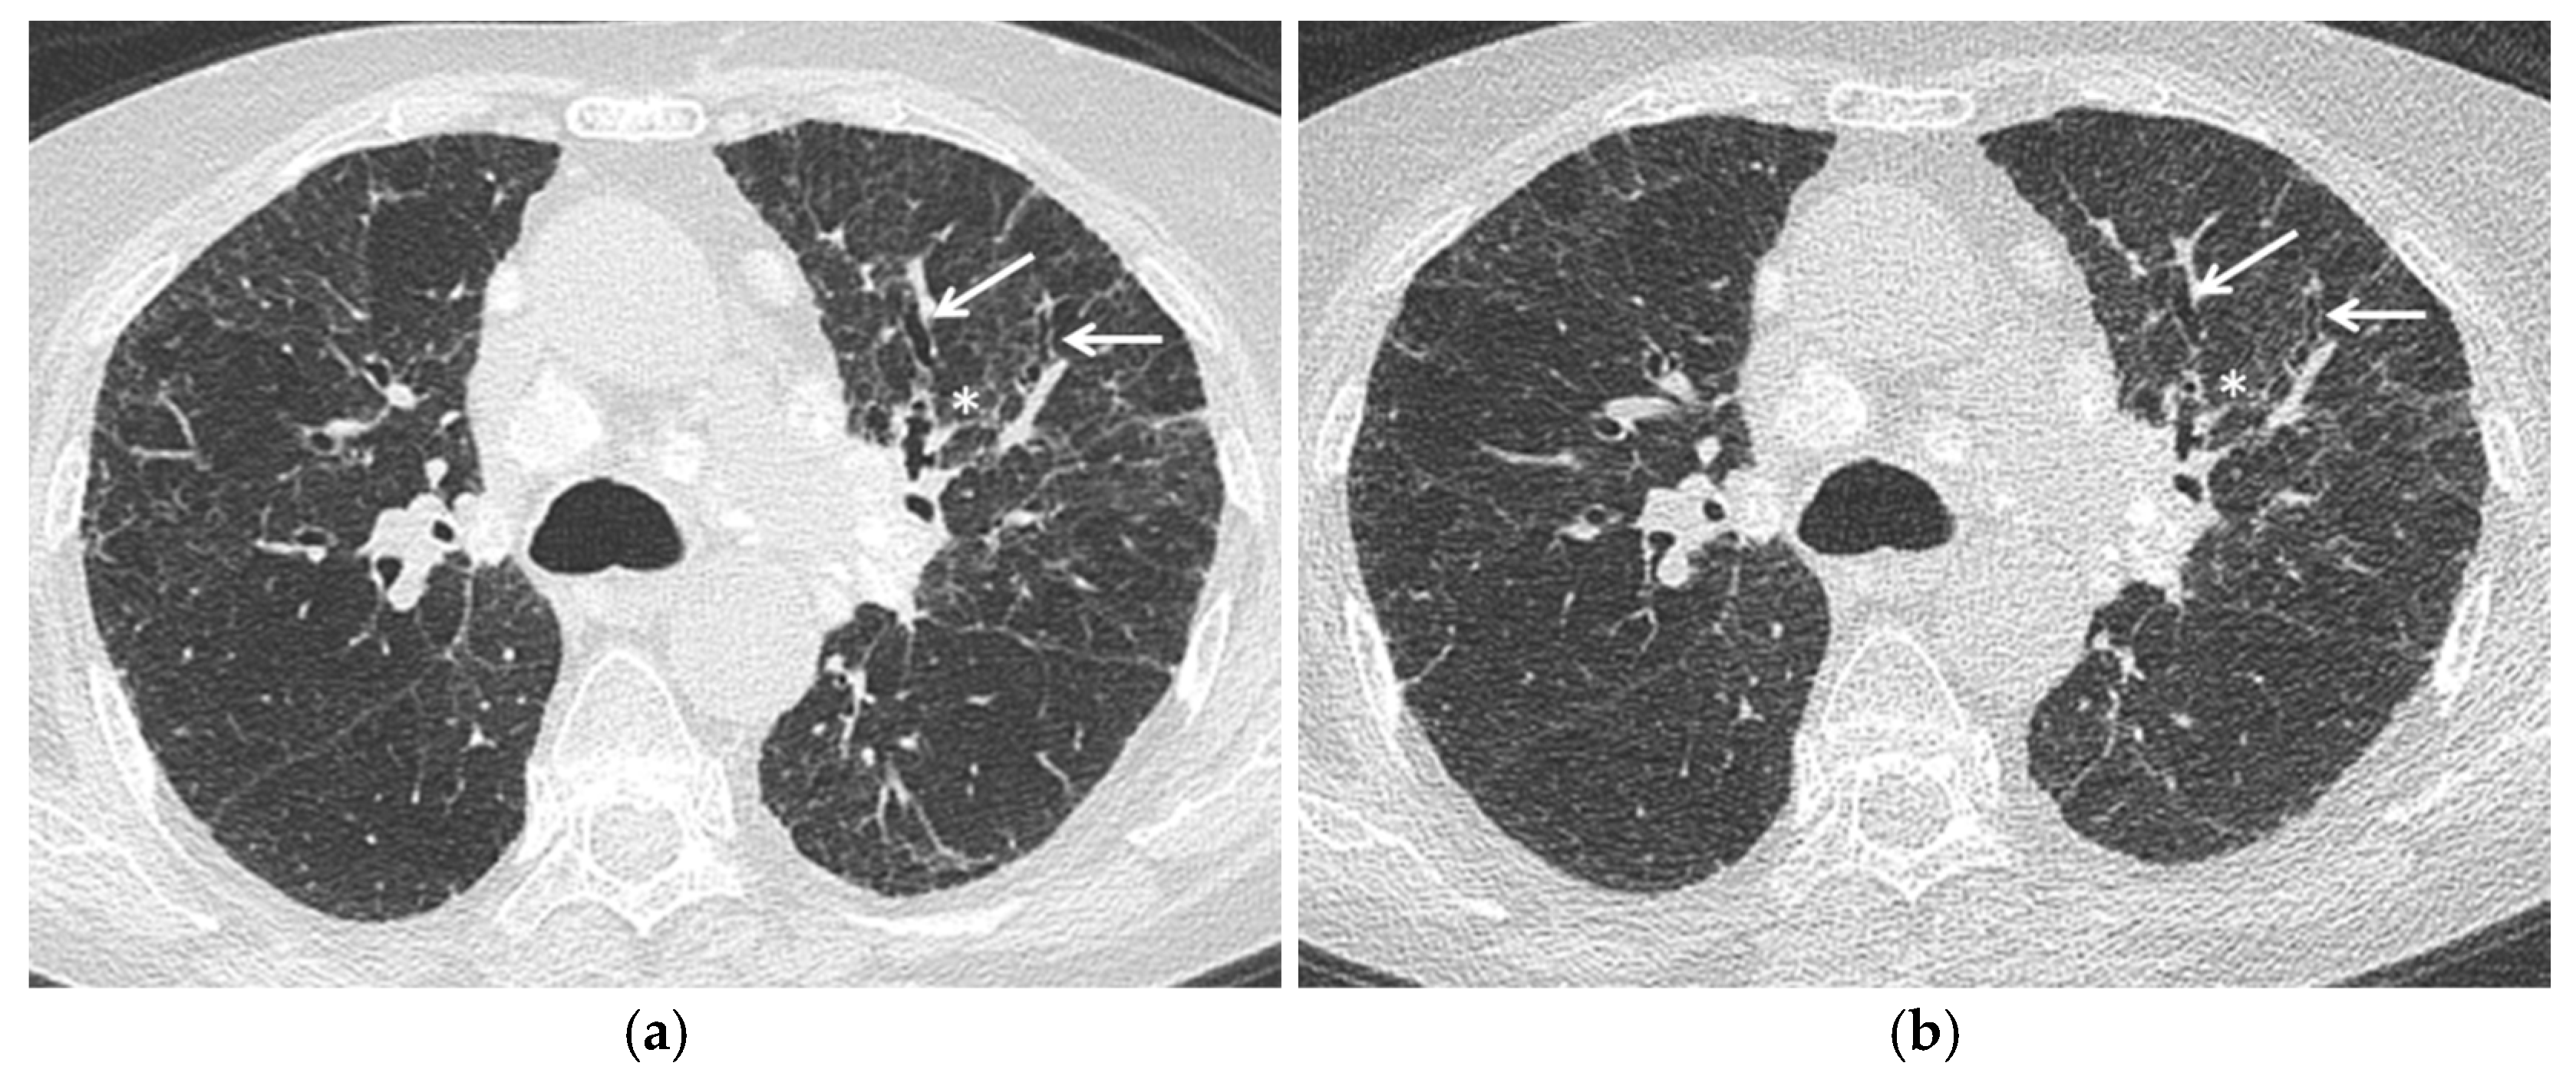

Diseases Free FullText Mosaic Pattern of Lung Attenuation on Chest Popcorn Lung On Ct Scan Lung tissue biopsy, which often requires an open lung surgical procedure, is necessary to confirm the diagnosis of bronchiolitis obliterans. They may also use a pulmonary function test. Bronchiolitis obliterans (bo), also known as obliterative bronchiolitis, constrictive bronchiolitis and popcorn lung, is a disease that results in. If you have some of the symptoms of bronchiolitis obliterans, your doctor might. Popcorn Lung On Ct Scan.